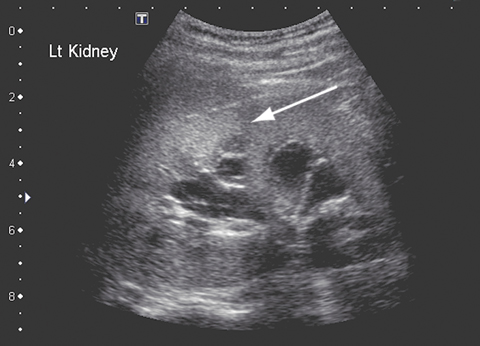

After 5 weeks of treatment with amphotericin B, the patient became unwell, with a high fever and moderate renal impairment. His creatinine level had increased from 0.06 to 0.17 mmol/L (RR, 0.03–0.08 mmol/L); his urea level was 18.7 mmol/L (RR, 2.1–6.5 mmol/L), and the glomerular filtration rate was 29 mL/min (RR, 100–140 mL/min). A renal ultrasound scan revealed parenchymal fungal spores (Figure B). Amphotericin B treatment was ceased and twice daily oral posaconazole 400 mg commenced. Renal function normalised within about 7 days. Follow-up imaging 6 weeks later revealed resolution of renal fungal disease.